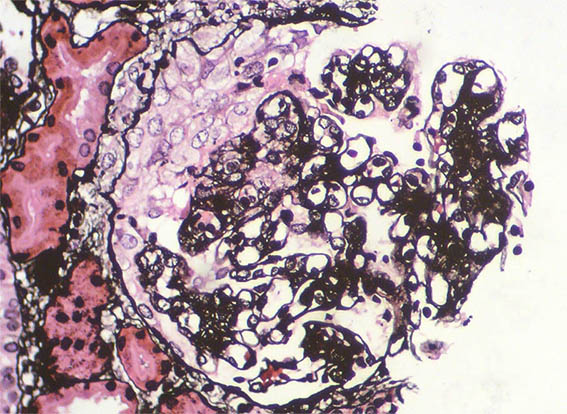

Figure 7. Methenamine-silver, X400.